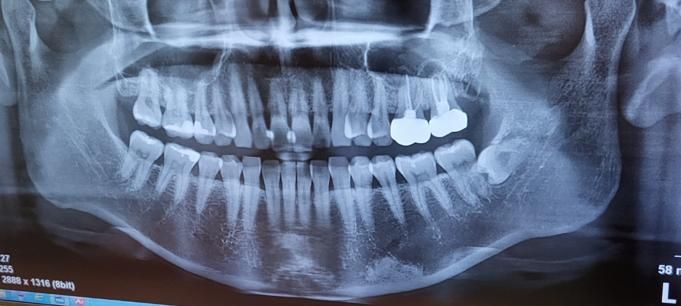

왼쪽 아랫니 부분인데 지금 치과를 2군데 다녀왔는데 어떤 곳은 이상이 없다고 하고 어떤곳은 치아 양쪽이 충치라 인레이 ㄱ모양으로 하고 그 옆은 레진으로 해야한다고 해서 누구말을 믿어야하나요..?

• 1번 째 사진

정확한건 치아 작은 사진을 찍어보시는게 좋을것같습니다. 치아 사이에 충치가 조금 잇어 보이긴합니다.

사진으로 봤을 경우 미세한 음영이 보입니다. 초기 충치일수 있으며 초기 충치일경우에는 양치질이나 치실을 이용해서 관리르 할수 있는 경우도 있습니다.

1. 작은 엑스레이사진(치근단사진)이 보다 해상도가 좋습니다. 작은 사진 보시면 약간 충치가 있어보이긴 합니다

2. 다만 당장 적극적인 치료가 필요한 정도의 큰 충치는 아닌 것으로 보입니다.